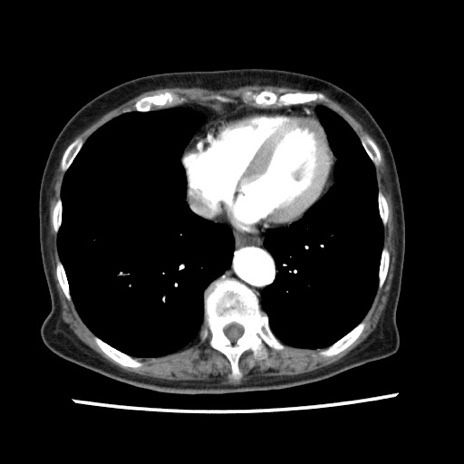

矢状断像

【症例】80歳代女性

【主訴】腹痛

【現病歴】8時間前から腹痛あり来院。

【既往歴】糖尿病、脂質異常症、子宮体癌にて子宮全摘術

【身体所見】意識清明・会話良好だが腹痛で苦悶様、全腹部にわたって反跳痛と圧痛あり

【データ】WBC 13600、CRP 0.14、LDH 224、CK 90